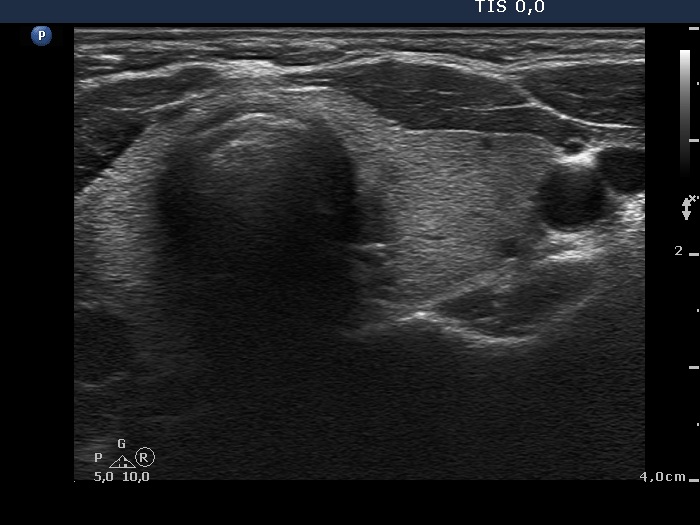

Initial examination (first row of images):

Clinical presentation: A 39-year-old woman was referred for evaluation of neck complaints lasting for more than a month. The patient had fever, neck pain. She has got two courses of antibiotics and non-steroid anti inflammatory drugs which had no effect.

Palpation: The right lobe was painful and hard while the left lobe was tender.

Laboratory examination: TSH 0.01 mIU/L, FT4 29.1 pM/L, FT3 7.45 pM/L, CRP 31.2 mg/L.

Ultrasonography: The thyroid presented with hypoechoic areas which had blurred borders. The echogenicity index was approximately 65% in the right and 20% in the left lobe. The thyroid was almost completely avascular.

Diagnosis: subacute, granulomatous de Quervain's thyroiditis.